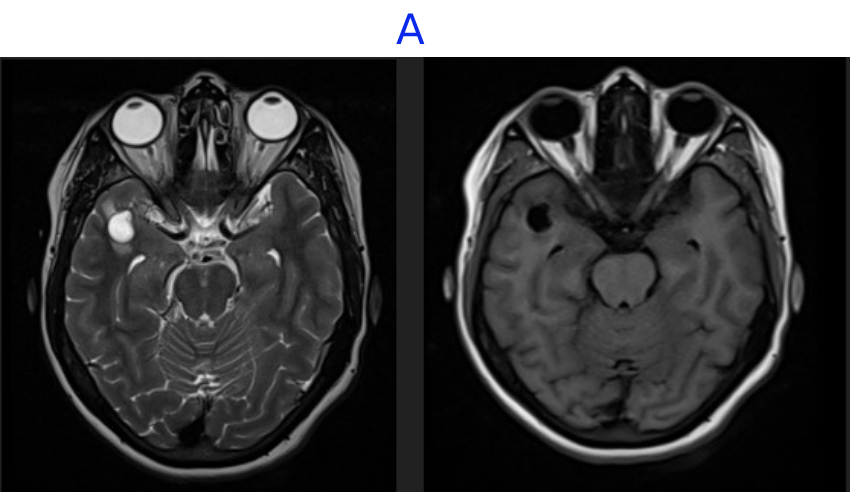

A. FINDINGS - MR BRAIN

• A. A well-defined, intra-axial, T2 hyperintense, T1 hypointense lesion measuring 14 x 12 x 9mm noted in the subcortical white matter of the peri-Sylvian right anterior temporal lobe